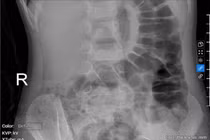

Từ triệu chứng lâm sàng và hình ảnh thuốc do gia đình cung cấp, các bác sĩ chẩn đoán các bệnh nhi bị ngộ độc thuốc Haloperidone mức độ trung bình. Sau 2 ngày điều trị tích cực, sức khỏe các trẻ dần ổn định, tri giác cải thiện, các cơn co giật được kiểm soát.

Bé gái 5 tuổi bị táo bón kéo dài gây tiểu dầm hàng đêm

Tình trạng táo bón, ứ phân kéo dài có thể chèn ép bàng quang gây tiểu dầm

Bệnh viện Đa khoa Medlatec vừa thăm điều trị cho bé T.H.B.H., 5 tuổi mắc chứng tiểu dầm từ nhỏ.